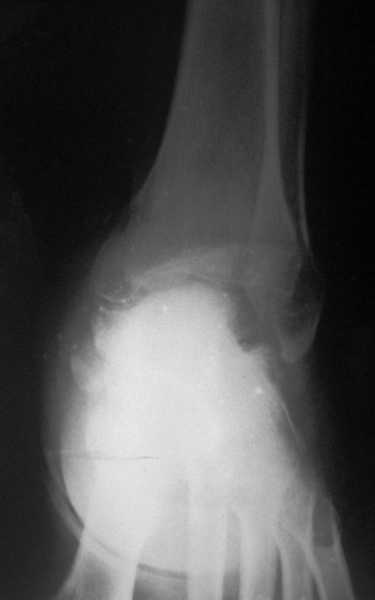

Среди повреждений таранной кости (Hawkins III-IV) с одновременной травмой лодыжек встретилось следующее (см. вложение). Пациент упал в колодец на глубину 10 метров (Х.2002 г.), госпитализирован с диагнозом: з/перелом шейки правой таранной кости (Hawkins IV) с переломовывихом тела назад и кнутри, закрытый перелом внутренней лодыжки и переднего края большеберцовой кости. Оперирован в первые 12 часов после травмы, выполнена открытая репозиция таранной кости, внутренним и передне-внутренними доступами, остеосинтез переломов шейки и тела губчатыми винтами, для реваскуляризации тела таранной кости первичный компрессионный над- и подтаранный артродез. Синтез внутренней лодыжки губчатым винтом. Удаление винтов через 1 год,2 мес. Получен анкилоз указанных суставов с сохранением длины конечности, полная реваскуляризация таранной кости, о чем говорит сращение ее переломов, отсутствие отеков и

цианоза стопы и голени. Компенсаторная подвижность переднего и среднего отделов стопы около 15-20 градусов за счет поперечного (Шопара) сустава стопы. Считаю оправданной подобную тактику, не смотря на угрожаемый прогноз (100% асептический некроз) по классифицкации Hawkins.